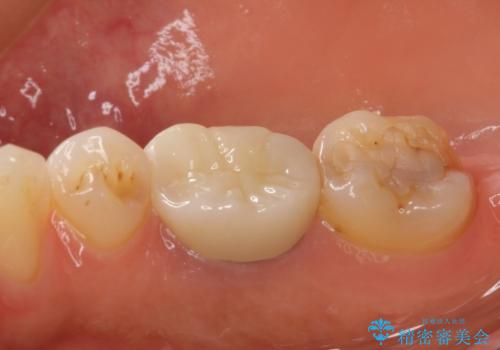

根管治療を行った奥歯は、再発防止や残された歯質を守るため、クラウンによる補綴治療が必要となります。

補綴後6か月経過しレントゲンを撮影したところ、根尖周辺の病変が消失していることが確認できました。